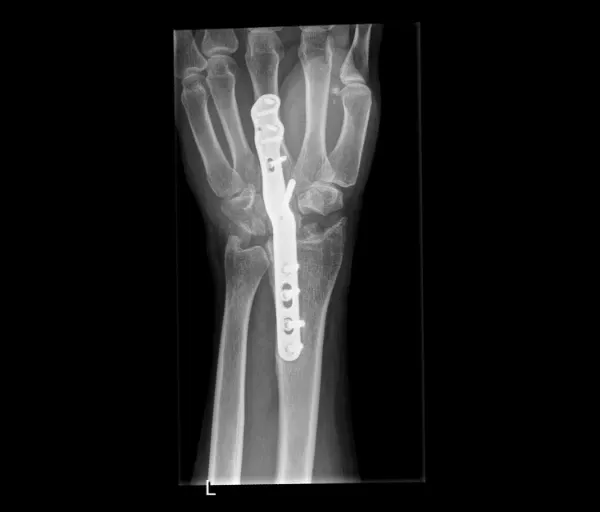

Operatief

Indien de breuk verplaatst is of onvoldoende stabiel:

- Pinnen (Kapandji-techniek): metalen pinnetjes door de huid, blijven 6 weken; risico op lichte inzakking

- Plaat en schroeven: meest gebruikte techniek; geeft meer stabiliteit en kortere gipsperiode; plaatje hoeft meestal niet verwijderd te worden

- Externe fixator: uitwendig frame, gebruikt bij open breuken

Alle ingrepen gebeuren via het chirurgisch dagziekenhuis, meestal onder plexusverdoving.